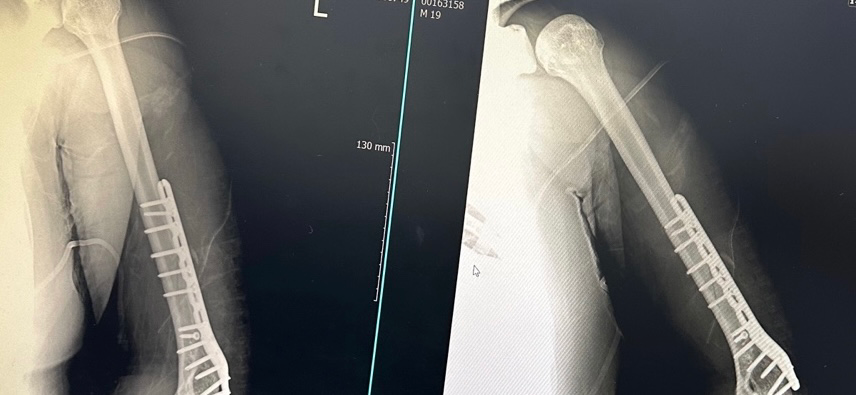

해당 수술시 자주 발생할 수 있는 후유증 중에 하나로

요골신경이 일부 눌리거나 손상되면서 해당증상이 나타날 수 있습니다.

우선은 해당 의료진에게 증상에 대해 알려주시고 재활 등을 하시면서 증상이 지속되거나 필요시 추후 근전도 검사로 신경이상 여부를 체크해 보시는 것이 좋겠습니다.